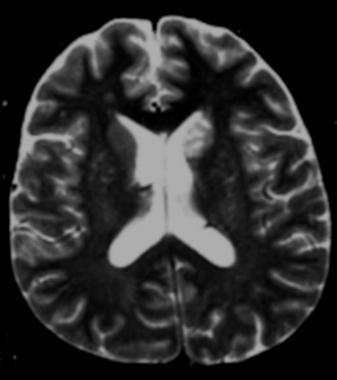

Axial T2-weight MRI shows clustered hyperintensities in the left caudate; these are consistent with enlarged Virchow-Robin spaces caused by small cryptococcomas